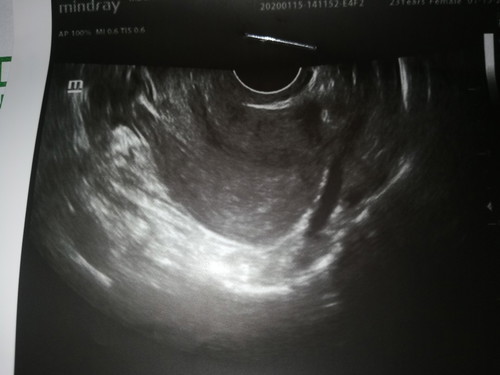

Hi! How many weeks will the baby appear on the ultrasound? As per this application, I am currently 6 weeks and 6 days pregnant and I took a Serum test as well and it is positive. I took a TransV yesterday but my uterus is clear and there is no trace of pregnancy yet. I have PCOS before. Maybe it is too early for the baby to be detected on the ultrasound? Is it possible that I conceived later than the computed dates?

Hi, I also had my transV last July 3 (6week and 6days too) but it appears like this and it has heartbeat. ❤